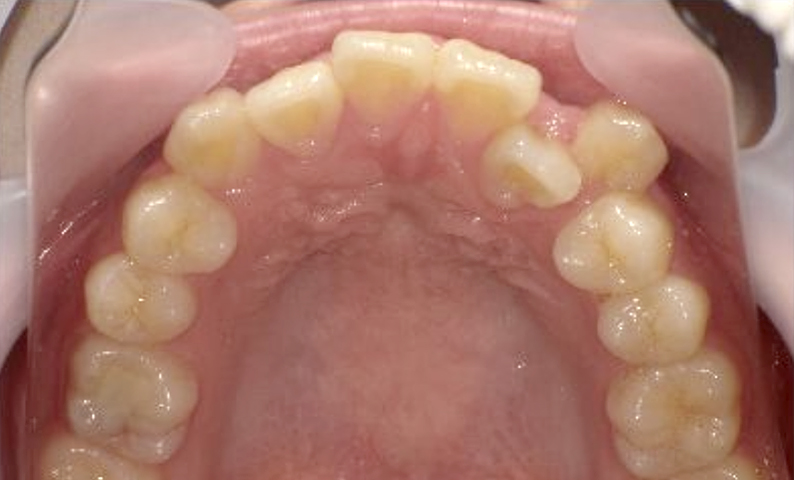

症例_021 上顎だけの部分矯正

治療期間:8ヶ月金額:30万円+税女性前歯のガタガタ八重歯上の前歯だけ

| Before | After |